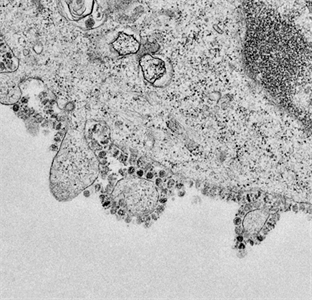

Các triệu chứng, phòng ngừa bệnh do Virus Marburg gây ra

(QK7 Online) - Marburg là bệnh đặc biệt nguy hiểm, khả năng lây truyền và tỉ lệ tử vong cao từ 50 - 88%.